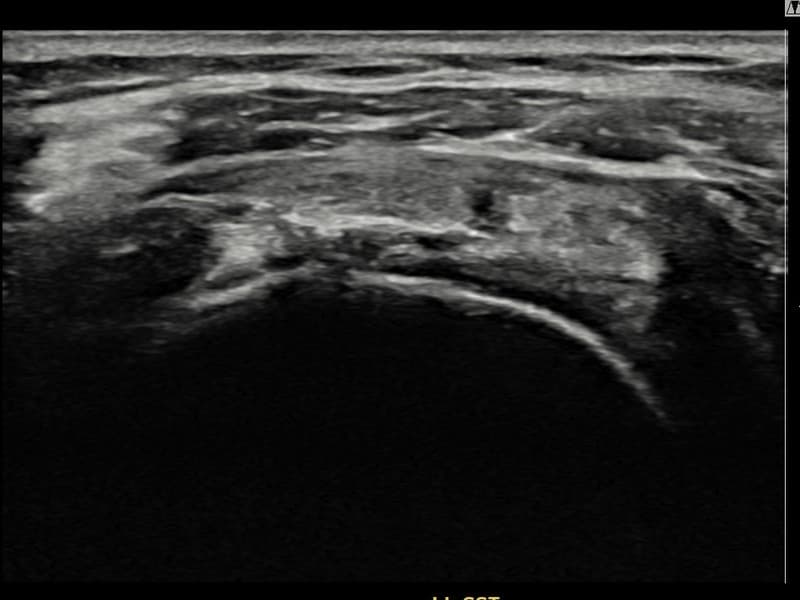

After

시술 전 초음파 측정 결과 파열 크기는 14mm × 7mm (힘줄 두께의 약 65% 결손)로 확인되었습니다. 시술 전 초음파에서 좌측 극상근건 점액낭면측의 광범위한 에코 소실과 힘줄 경계의 불규칙성이 확인되었습니다. 시술 후 초음파에서 힘줄 경계가 정상화되고 에코 패턴이 균질하게 회복된 것이 관찰되었습니다.

50대 초반 여성 환자분으로, 가사 노동과 직장 업무를 병행하며 왼쪽 어깨 통증이 점점 심해져 내원하셨습니다. 초음파 검사에서 좌측 극상근건 점액낭면측의 광범위 부분파열이 확인되었으며, 파열 면적이 넓어 일반적인 보존적 치료로는 구조적 회복이 어렵다고 판단하였습니다. 초음파 유도 하 축소봉합술을 시행하였고 시술 당일 귀가하셨으며, 이후 체계적인 재활 프로그램을 진행하였습니다. 시술 13주 후 추적 초음파에서 힘줄 연속성이 안정적으로 회복되고 점액낭면측 경계가 정상화된 것이 확인되어 통증 없이 직장 복귀에 성공하셨습니다.